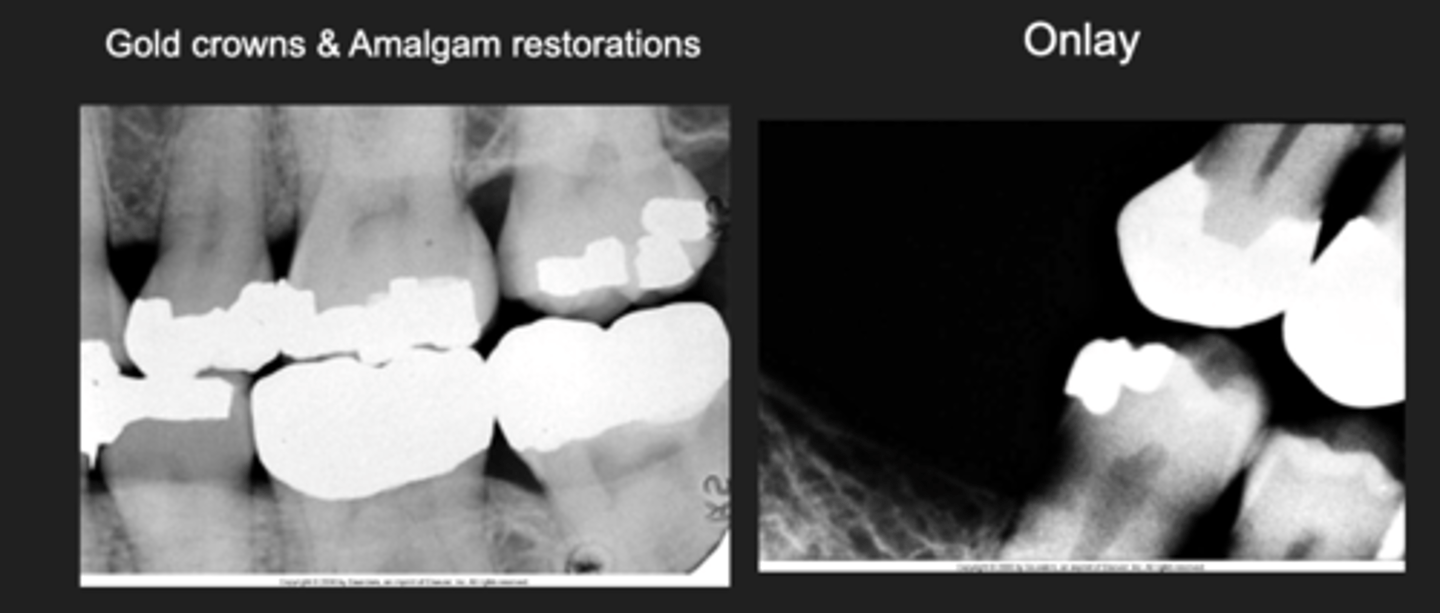

Gold restorations

Radiopaque

- Gold crowns and bridges

- Gold inlays and onlays

Gold crowns, amalgams example

Gold restorations examples

- Gold crowns and amalgam restorations and onlay